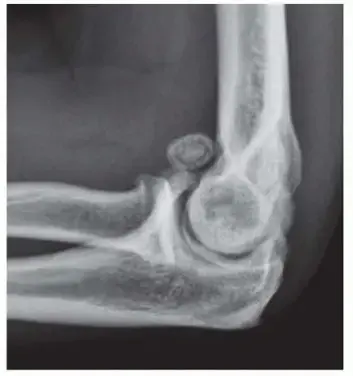

1. الأشعة السينية (X-rays):

• تعتبر الأشعة السينية هي الخطوة الأولى والأكثر شيوعاً.

• على الرغم من أن خشونة المرفق قد تحافظ على مسافة مفصلية طبيعية نسبياً، إلا أن الأشعة السينية يمكن أن تكشف عن وجود النتوءات العظمية (bone spurs) حول المفصل.

• كما أنها تساعد في استبعاد أسباب أخرى للألم مثل الكسور أو الأورام.